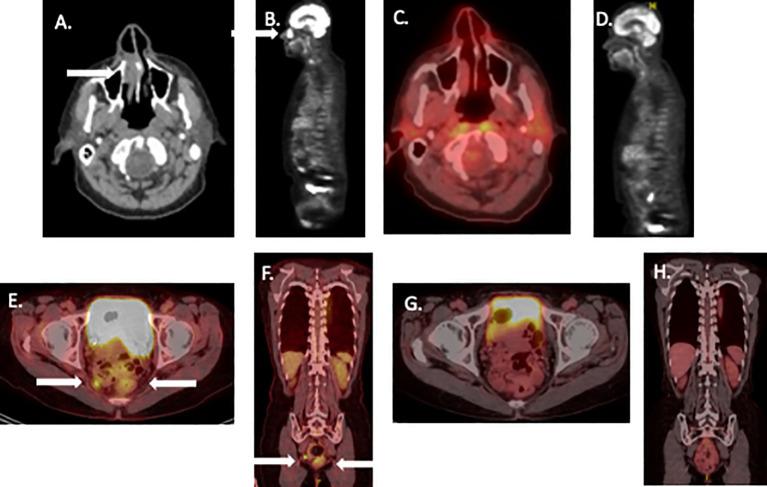

Mucosal melanoma represents an uncommon melanoma subtype. Wide excision has long represented the standard therapeutic approach. Unfortunately, there is a high relapse rate and mortality. Neoadjuvant therapy with ipilimumab plus nivolumab has shown significant activity in cutaneous melanoma. We present two cases of mucosal melanoma, each with potential regional dissemination, who were treated with neoadjuvant immunotherapy with minimal toxicity. Both patients were closely monitored and achieved radiologic and pathologic complete responses. These patients were able to avoid radical surgery and related functional consequences. Both patients remain recurrence-free with protracted follow-up. The potential usefulness of neoadjuvant immunotherapy as an organ preservation strategy in mucosal melanoma deserves further evaluation in prospective clinical trials.

黏膜黑色素瘤是一种罕见的黑色素瘤亚型。长期以来,广泛切除一直是标准的治疗方法。不幸的是,其复发率和死亡率很高。伊匹木单抗加纳武单抗的新辅助治疗已在皮肤黑色素瘤中显示出显著疗效。我们报告了两例黏膜黑色素瘤病例,每例都有潜在的区域播散,接受了毒性极小的新辅助免疫治疗。两名患者均受到密切监测,并实现了影像学和病理学完全缓解。这些患者得以避免根治性手术及相关功能后果。经过长期随访,两名患者均无复发。新辅助免疫治疗作为黏膜黑色素瘤器官保留策略的潜在效用值得在前瞻性临床试验中进一步评估。